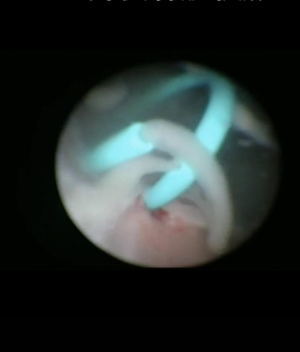

置入输尿管内支架后,脓液喷涌而出(术中照片)